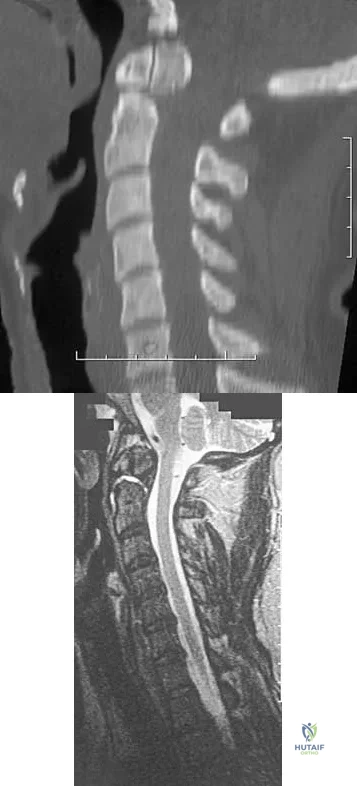

A 42-year-old woman reports that she has low back pain and had a transient loss of consciousness after falling off a horse. She denies having neck pain but notes that she was involved in a motor vehicle accident 2 years ago and had neck pain at that time. Examination reveals full range of motion of the neck and no localized tenderness. The neurologic examination is normal. A lateral radiograph of the cervical spine is obtained. Figures 41a and 41b show CT and MRI scans. What is the most likely diagnosis?

Explanation

A patient who has had neck pain radiating down the arm for the past 4 weeks reports that the pain was excruciating during the first week. Management consisting of anti-inflammatory drugs and physical therapy has decreased the neck and arm symptoms from 10/10 to 3/10. He remains neurologically intact. MRI and CT scans are shown in Figures 5a and 5b. The best course of action should be

Explanation

A 65-year-old woman has significant neck pain after falling and striking her head. A radiograph and sagittal CT scan are shown in Figures 23a and 23b. What is the most likely diagnosis?

Explanation